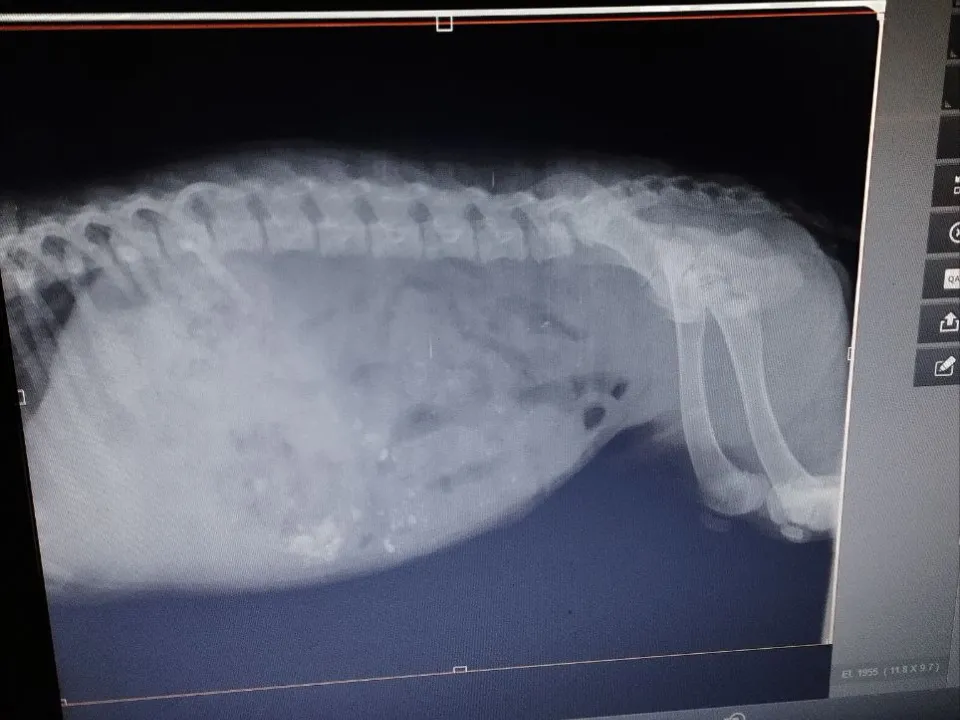

Шарика накормили костями какие-то недальновидные люди: желудок забился, живот сильно раздуло. Наталья отметила, что собакам нельзя давать кости, особенно вареные, так как они могут проткнуть кишечник и вызвать перитонит.

Общими усилиями удалось поймать щенка и отвезти его в ветклинику, где ему оказали первую помощь. Сейчас сдали все анализы и ждут результатов, чтобы понять, нужно ли хирургическое вмешательство.